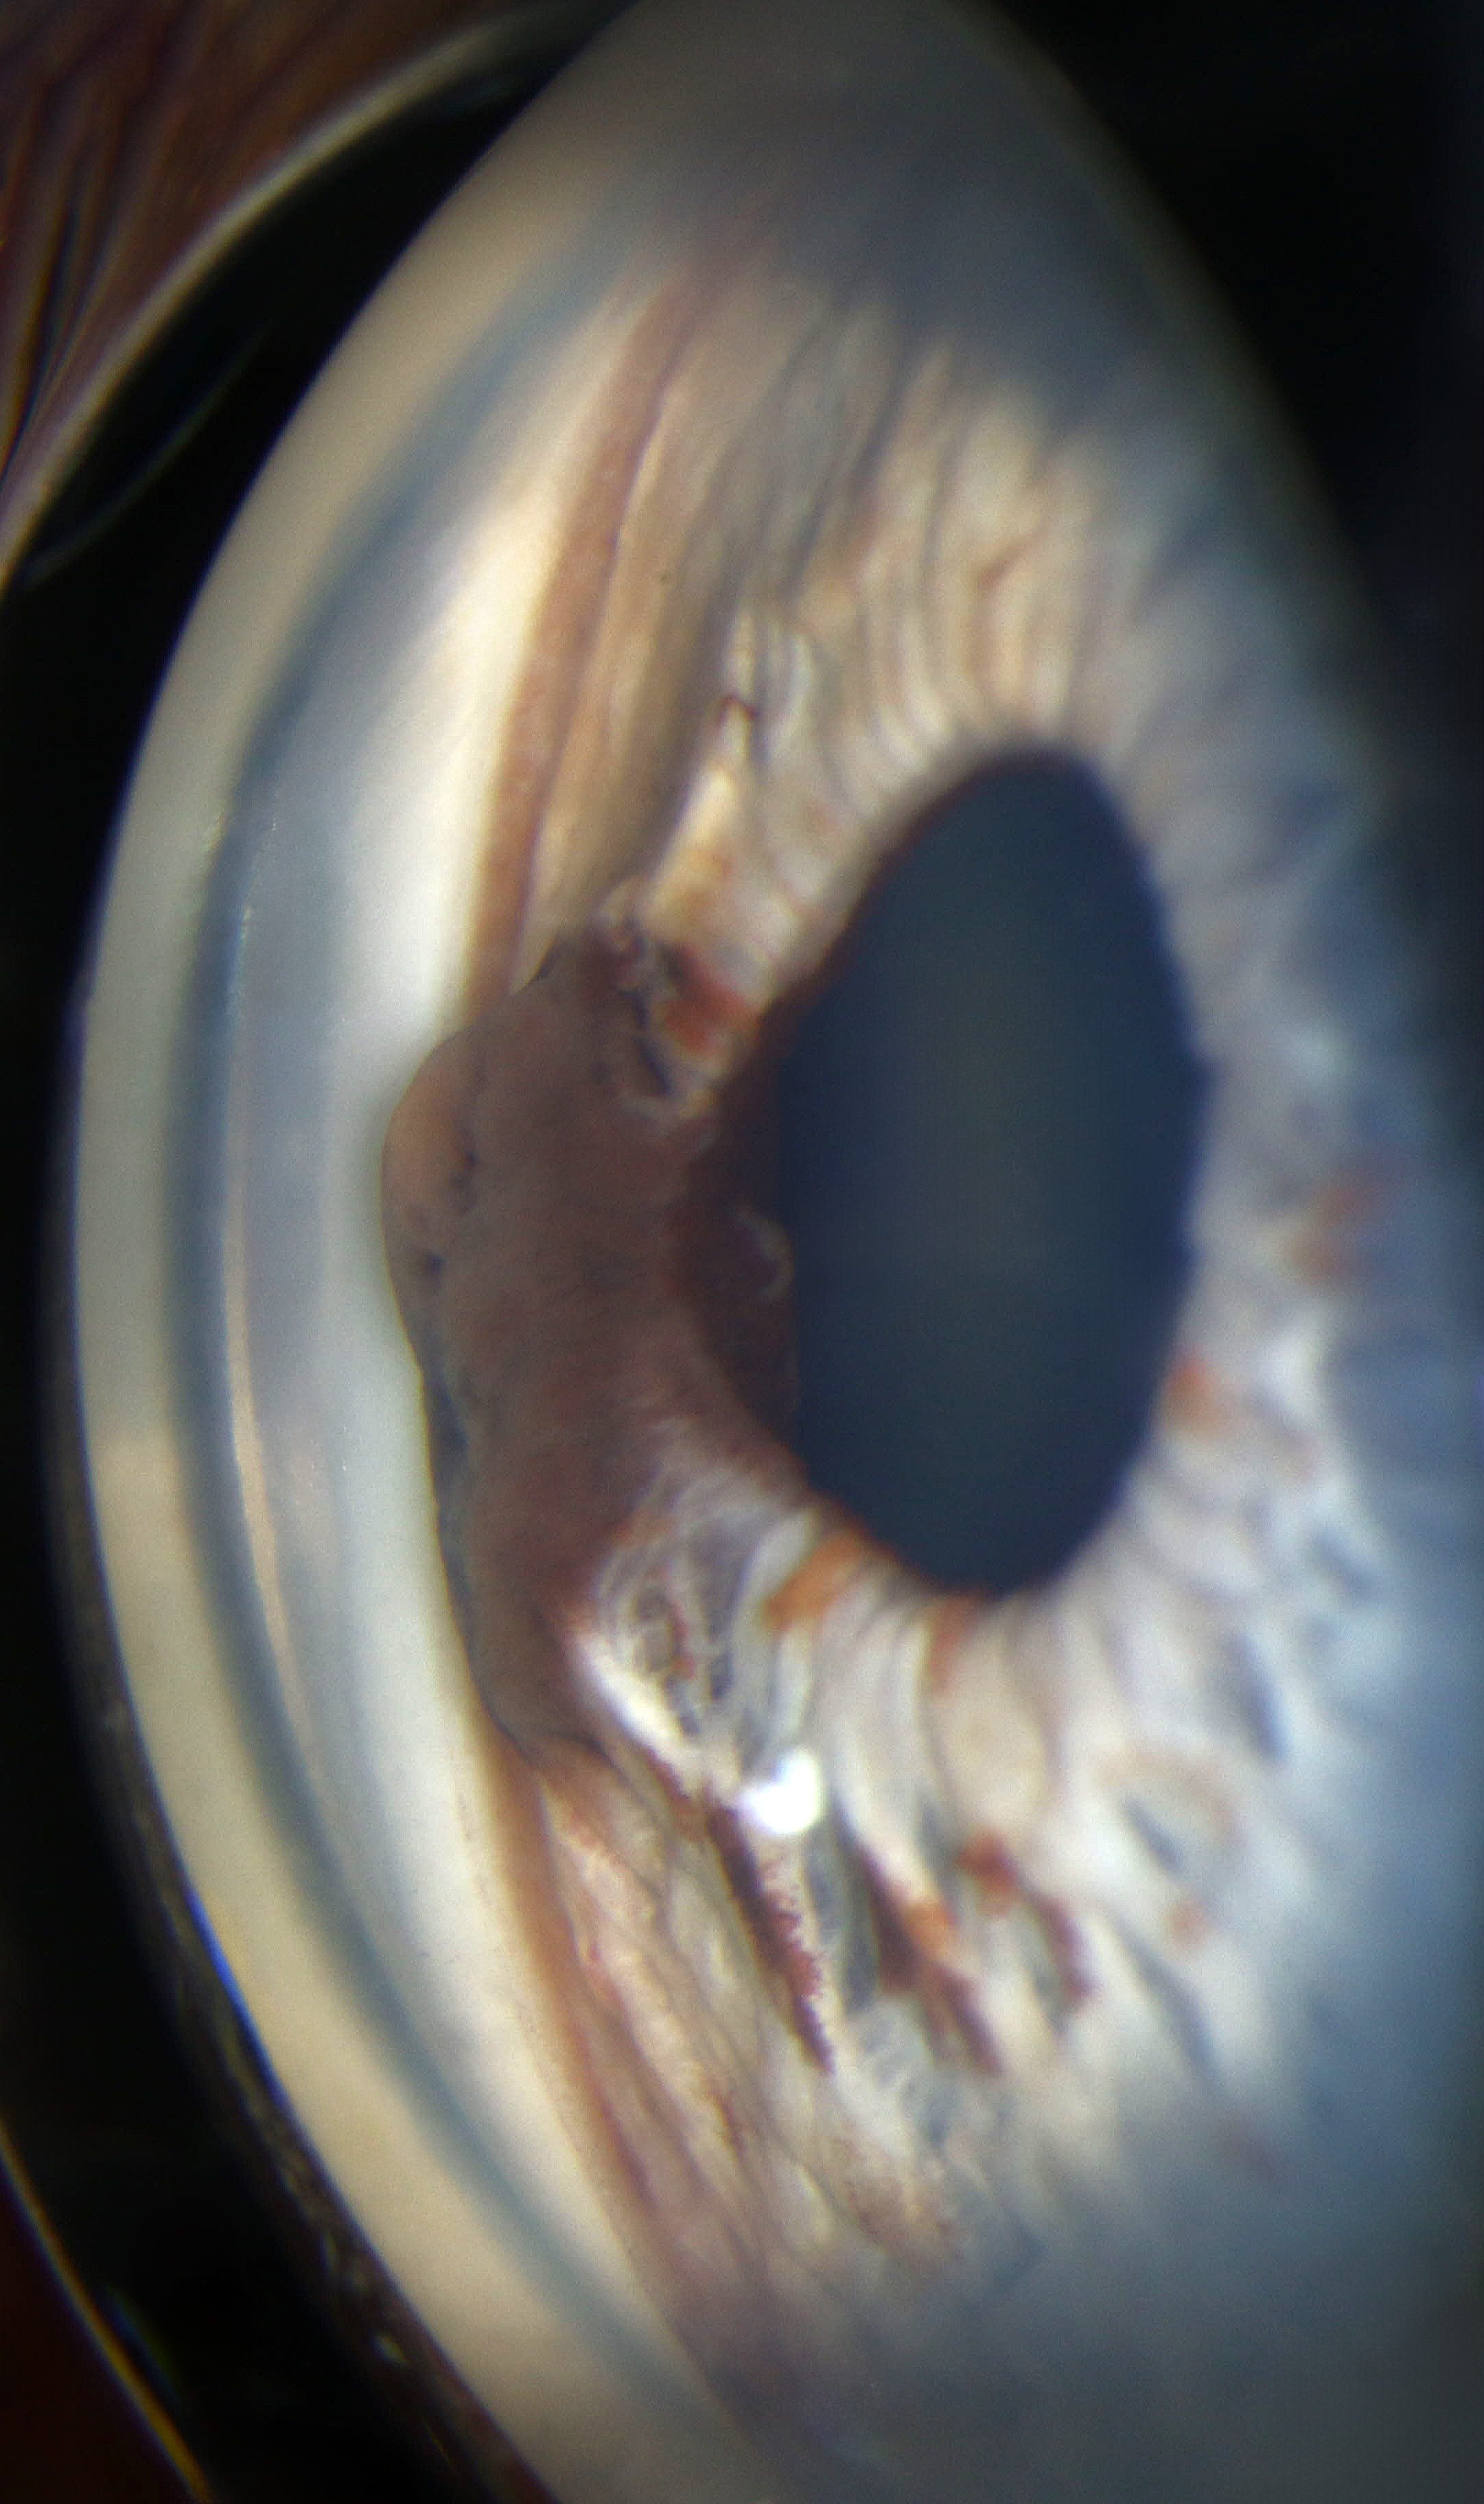

Iris Lesion Presented by John Head This photograph received First Place, Gonio Photography in the 2025 OPS Scientific Exhibit. Filed Under Cornea OPS Photo